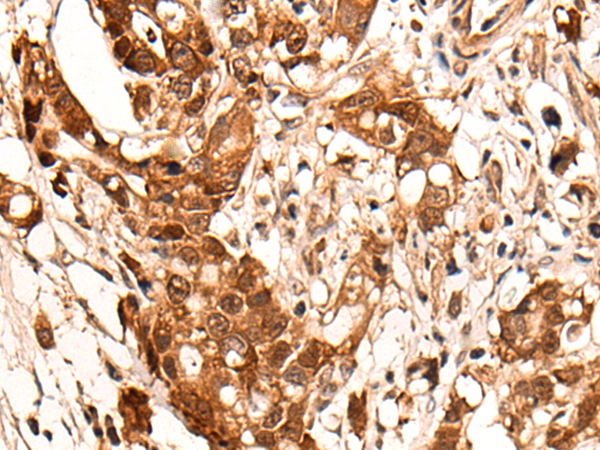

IHC positive control: |

Human ovarian cancer and human gastric cancer |